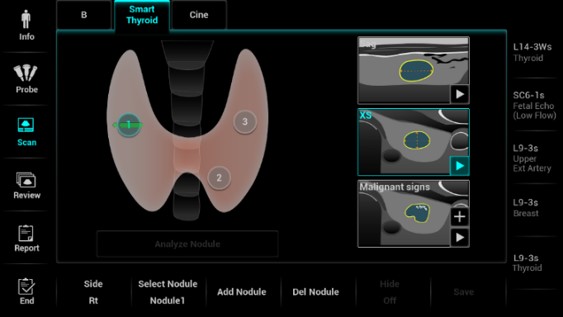

Smart Thyroid - Inteligentný protokol štítnej žľazy + analýza TI-RADS

Smart Thyroid – software umelej inteligencie: Automatické vyhľadanie lézie a jej ohraničenie. Štandardizovaný protokol detekcie lézií v oboch rovinách Automatická TI-RADS analýza. Presná a plne automatická detekcia lézií s obkreslením a pomeraním, TI-RADS analýzam a vytvorenie report. Urobí vaše klinické rutinné UZV skenovanie štítnej žľazy PRESNEJŠIE, RÝCHLEJŠIE a JEDNODUCHŠIE.

Smart Thyroid - Inteligentný protokol štítnej žľazy + analýza TI-RADS